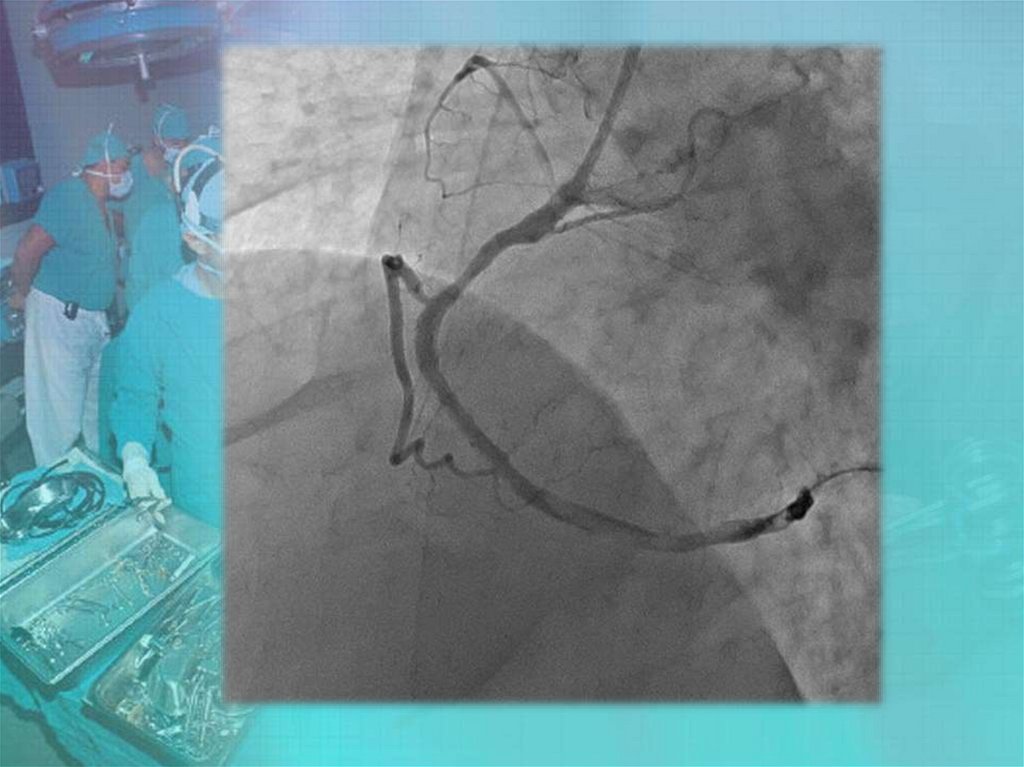

Коронары. СНК кафедры факультетской хирургии №2 лечебного факультета